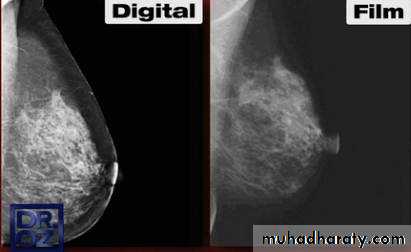

A digital mammography system tends to require a lower radiation dose than film screen mammography for the same image quality. Digital detector converts the X-ray photons to an electronic signal, which is further processed and displayed as a gray scale image. This image can either be electronically sent to a viewing station and displayed on a high-resolution monitor or printed and read on luminant-view boxes similar to how the film screen mammograms are read.

The digital system provides greater contrast resolution and thus better visualization of skin, peripheral breast tissue, and dense breasts. Besides this, it allows for changes in zoom, contrast, and brightness, which increase the ability to detect subtle abnormalities.

A film screen system does not offer such facilities and also tends to suffer from artifacts during processing and storage. These deficiencies are, however, partly compensated for by the advantage of a higher spatial resolution in film screens as compared to digital systems. However, despite of all these technological differences, studies have shown that the overall diagnostic accuracy was similar with these 2 modalities except for premenopausal and perimenopausal women in whom digital mammography was found to be more accurate. This is at least partly because digital mammography is relatively more sensitive than film mammography in detecting cancer in dense breasts.